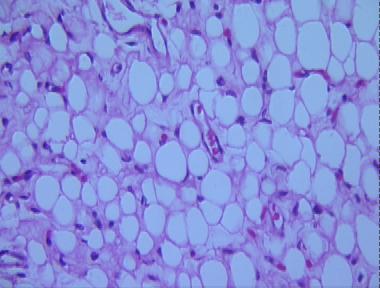

lipoblastoma

Histologic Features

- A multilobular neoplasm separated by prominent fibrous septae in the subcutis, characterized by

- A proliferation of lipoblasts that range from vacuolated spindle cells to larger cells with multiloculated cytoplasm and central nuclei, to small mature lipocytes

- More mature areas showing small lipocytes with peripheral spindle nuclei

- Scattered blood vessels without a vascular network

- Abundant mucoid matrix containing stellate spindle cells

- Scattered inflammatory cells such as lymphocytes within the neoplasm